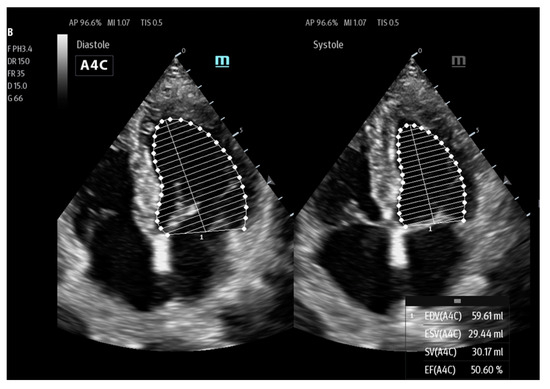

| Lvivo | Philips | automatic measurement of stroke volume (SV) and cardiac output (CO) | Ultrasonographic assessment of cardiac function |

| AutoVTI | GE | ||

| US2.AI | EchoNous | ||

| SmartVTI | Mindray | ||

| AutoEF | Mindray | calculation of ejection fraction (EF) | Ultrasonographic assessment of cardiac function |

| RealTimeEF | GE | ||

| LvivoEF | Philips | ||